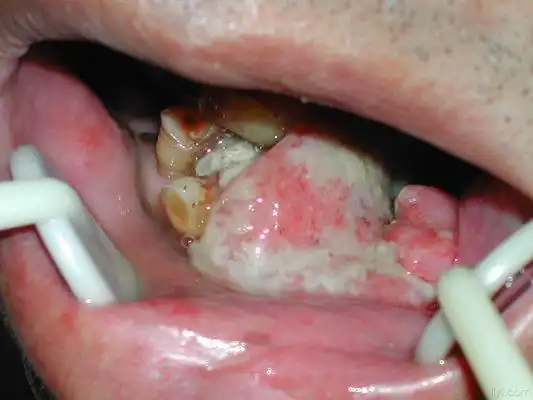

牙龈炎